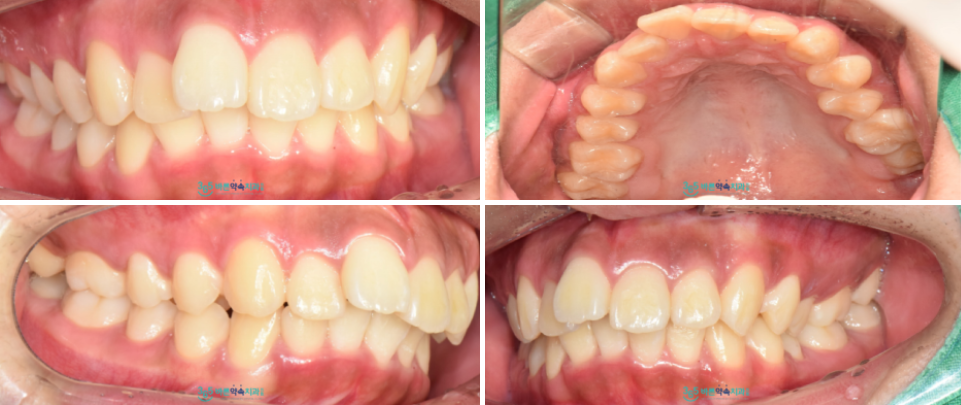

오늘 소개해 드릴 환자분께서는

10대 남학생으로

치아가 삐뚤어져 있고

튀어나와 있으시다며

교정 치료 상담을 위해

부모님과 함께 본원을 찾아주셨는데요.

구강 내를

확인해 보았더니

치아 배열이 고르지 않고

위턱 앞니가 앞으로 뻐드러져 있는 상태로

이는 우리가 흔히 부르는

앞니와 입 모양이 툭 튀어나와 보이는

돌출입이라 하며

아래턱 어금니가

위턱 어금니 보다 뒤쪽에 위치하는

2급 부정교합에 해당하는데요.